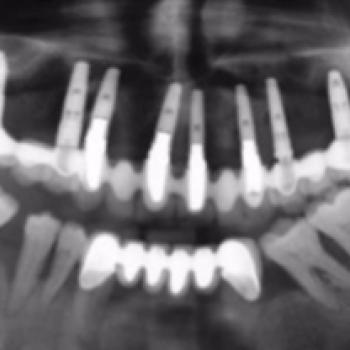

Importancia del mantenimiento en la evolución de un paciente con periodontitis agresiva y periimplantitis

La periodontitis agresiva se define como una enfermedad de rápida progresión en la destrucción periodontal que se presenta de dos formas: local y general (Armitage 1999). Se ha observado que la prevalencia de esta enfermedad es mucho menor en comparación con la periodontitis crónica siendo en algunas poblaciones de hasta un 28’8% (Albandar JM 2002).

Ante la pérdida temprana de piezas dentales, la rehabilitación con implantes ha sido considerada una de la opciones terapéuticas de elección. Según ciertos autores, estos pacientes son mas susceptibles de padecer periimplantitis influyendo directamente sobre la supervivencia de los implantes dentales (De Boever AL 2009).

Autores: Morera Cuenca M, Vázquez Pérez M, López Roldán A, Gil Loscos FJ, Buitrago Vera P, Alpiste Illueca F. Posgrado en Periodoncia y Osteointegración. Universidad de Valencia.